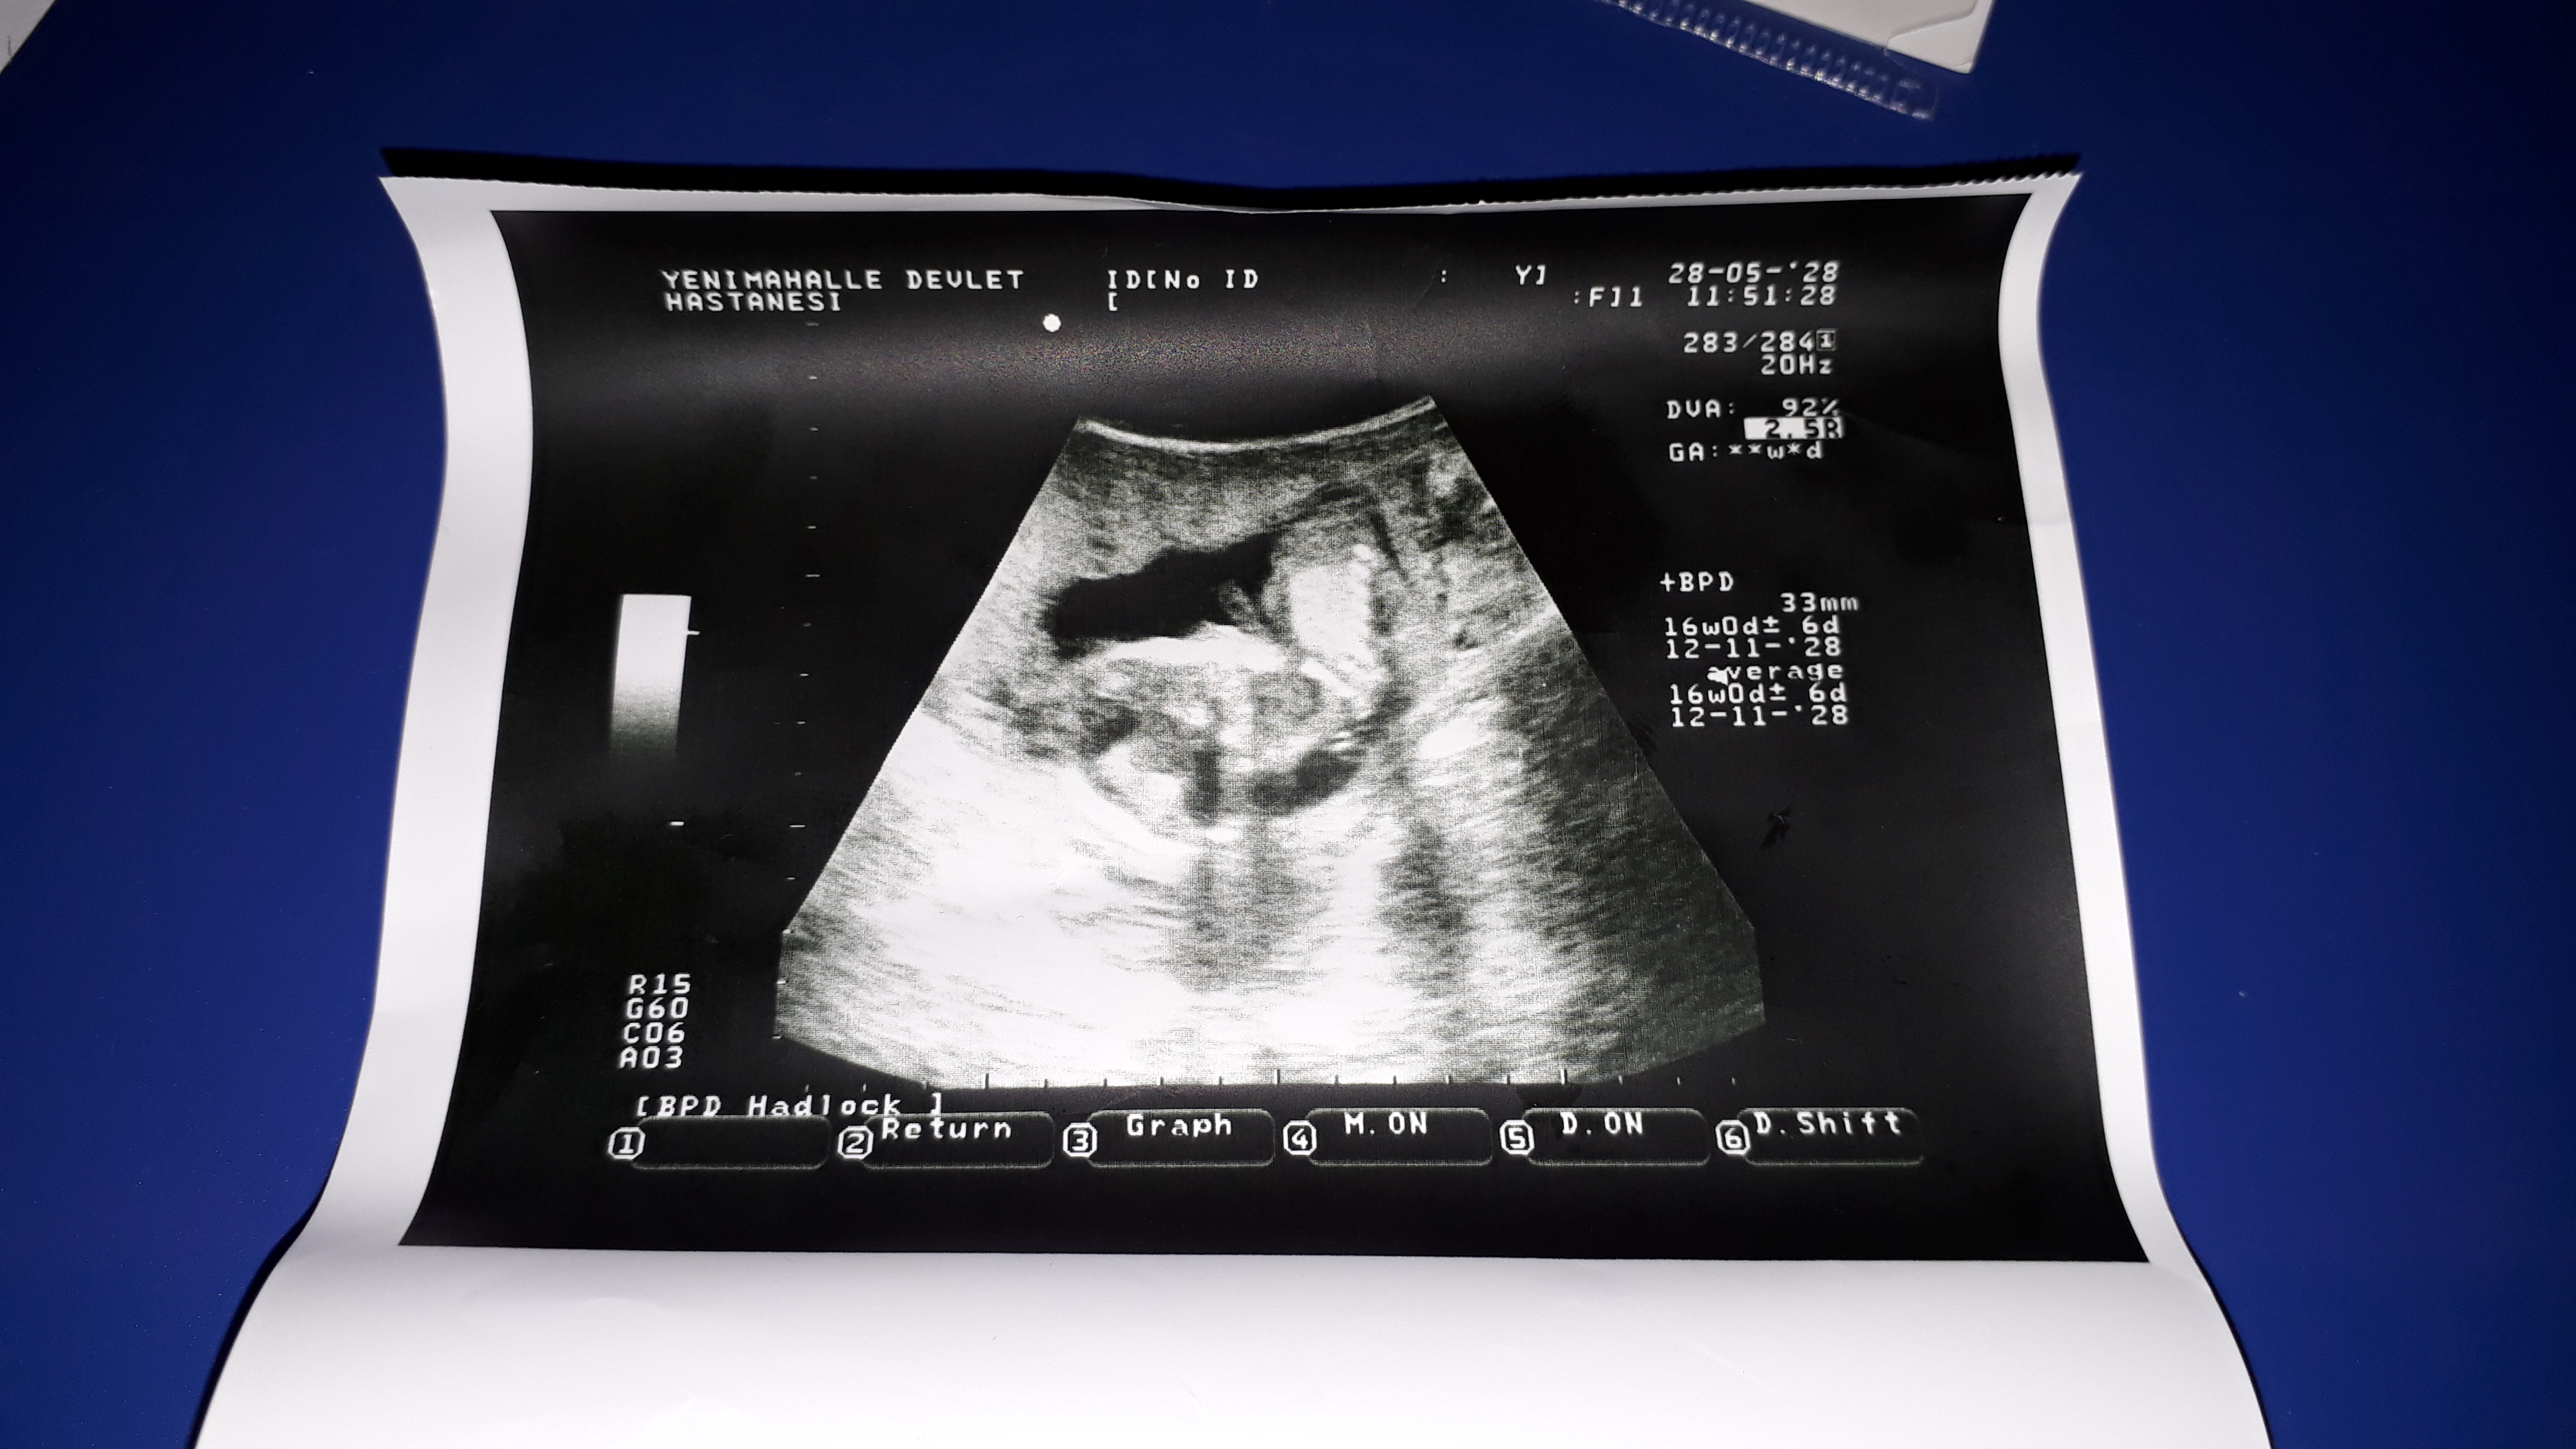

Benimkine de bakar mısınız

Resimde gördüğünüz gibi üst taraftaki çıkıntı paralel ise bebek kız, 30° lik açıyla yukarı bakıyorsa bebek erkektir.

Gebeliğin 9. haftası fetusun bacaklarının arasın da küçük bir çıkıntı görülür. Gebeliğin 12. ve 14 haftası bu topak çıkıntı nın açısı değerlendirilerek , cinsiyet tahmini yapılır. Çıkıntı kızlar da 30 derecenin altın da ve düzdür erkekler de ise 30 derecelik açıdan büyüktür.

Görünürlük , omurga ile ilgili genital tüberkül açısı , Gölgeler ve erkek belirteçler ve topak çevreleyen ucu , Gebelik yaşına göre uzunluğu da dahil olmak üzere, şekil.. Nub teorisi ile cinsiyet belirleme de tarama omurga görüntüleme ve buna özü ilişkisini sağlamak için, profil görünümünde olmalıdır.

Sevgili melisa ultrason resimleri ışıktan çabuk etkileniyor yüklemiş olduğunuz resimlerde nub çıkıntısı görülmüyor